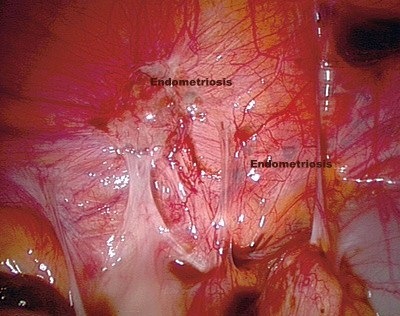

En la imagen se puede apreciar el interior de la cavidad pélvica. En ella, se identifican lesiones por endometriosis.

Fuente: Tidsskr Nor Laegeforen. 2008 Jun 26;128(13):1515-8.